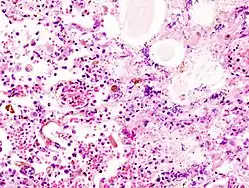

![]() Vævsprøve fra patient med aspirationspneumoni | |